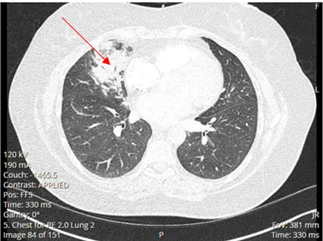

A 52-year-old Caucasian female, who is a resident of southwestern Ohio, presented to the emergency room with a chief complaint of a two-week history of right-sided chest pain, which had progressively worsened despite two courses of antibiotics and pain medications following her two recent visits to the emergency department. She also described subjective fever, shortness of breath, nonproductive cough and weight loss of 4 kg over the last two weeks. She was a smoker of ½ pack per day for 20 years and quit smoking 4 weeks ago. The patient’s past medical history includes anxiety, depression, gastroesophageal reflux disease, hypertension, mitral valve prolapse, and migraine headache. Her chest pain started in early September, and it was described as stabbing and pleuritic, which was also noted to be reproducible to palpation of the chest wall. She was seen first at the emergency department two weeks prior to the current presentation for evaluation of the right-sided chest pain. Still, at that time, there was no fever or cough, and her vitals were stable with Oxygen Saturation 94% on room air, although her laboratory testing was significant for leukocytosis with (WBC):16.6 K/UL with 68.5% neutrophils. Chest-X-ray demonstrated an infiltrate in the right lung base medially, while CT–chest angiography demonstrated no evidence of pulmonary embolism and right middle lobe consolidation consistent with pneumonia. There was no mediastinal or hilar lymphadenopathy, (Figures 1 and 2).

Figure 2. CT-chest angiography showing right middle lobe consolidation.